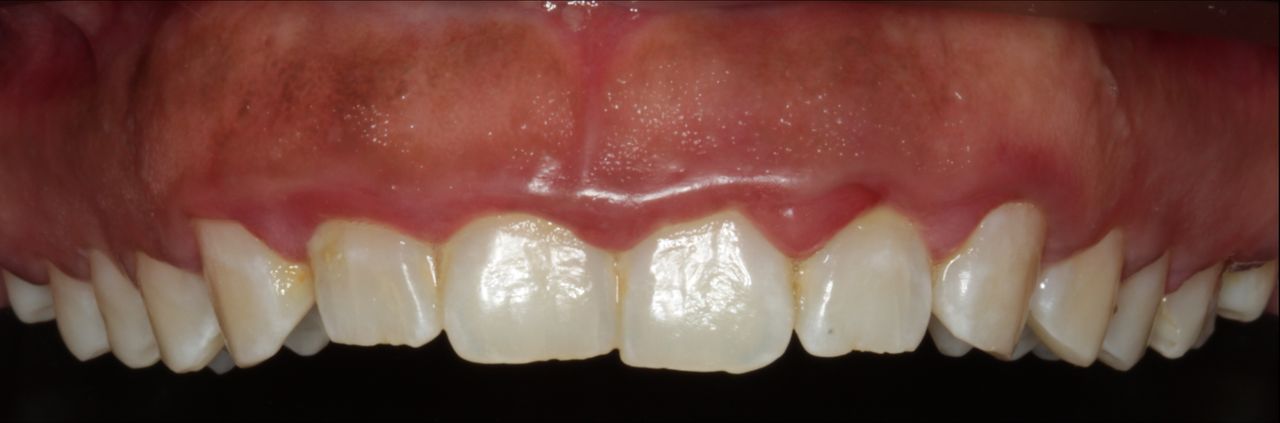

Fotos y videos

La enfermedad periodontal es una patología infecciosa, inflamatoria crónica, de origen bacteriano causada por una comunidad de microorganismos llamada biofilm dental que se adhieren a los dientes, provocando una respuesta inmunitaria que afecta a los tejidos que soportan al diente como el hueso alveolar, ligamento periodontal, cemento radicular. Si esta enfermedad no se controla nos lleva a la primera patología llamada gingivitis con signos clínicos inflamación, sangrado, enrojecimiento en las encías sin perdida ósea. Y si esta no se controla se asevera con presencia de periodontitis con signos clínicos de inflación, dolor, perdida de los tejidos de soportan al diente.